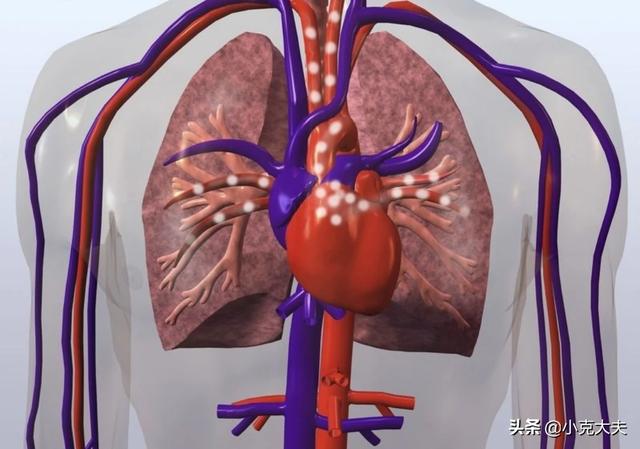

実は、その理由はとても単純で、水道管が詰まるのと同じように、遠くの方の水圧が足りなくなり、その結果、水の量が少なくなったり、あるいはまったく水が出なくなったりするのである。血管の詰まりも水道管の詰まりと同じで、血管は人間の血液の輸送路であり、酸素や栄養分を運ぶのに使われる。もし血管が詰まれば、遠位の組織は酸素や栄養分を待つことができなくなり、臓器虚血となり、手足のしびれや痛みなどの不調が生じ、命にかかわることさえある。

血管は水道管のようなもので、主に輸送のパイプラインである。血管が必要とするエネルギーは、心臓から送られる血液によって供給されるが、人々の血管が詰まったとき、主に詰まることによって引き起こされる血栓のために、人体に何らかの異常な変化があるだろう。

血管の閉塞は、水道管の閉塞で私たちの生活と同等であり、水道管は一度ブロックされ、より少ない水の流れになります、私たちの血管の閉塞も同じ理由であり、血管の閉塞は、臓器や組織の一部が正常に動作するのに十分な血液中の酸素を得ることができないにつながる、この時点で、体は私たちの血管の閉塞の問題を示唆するためにあらゆる種類の症状が表示されます。

血管は人体の血流の通り道であり、細胞の代謝に必要な酸素や栄養素を全身に運び、肺(二酸化炭素など)や腎臓(尿を濾過する)から代謝老廃物を除去している。従って、動脈、静脈、毛細血管からなる循環系は、正常な生理機能を維持するために非常に重要であり、血管が閉塞すると様々な機能障害が起こる。